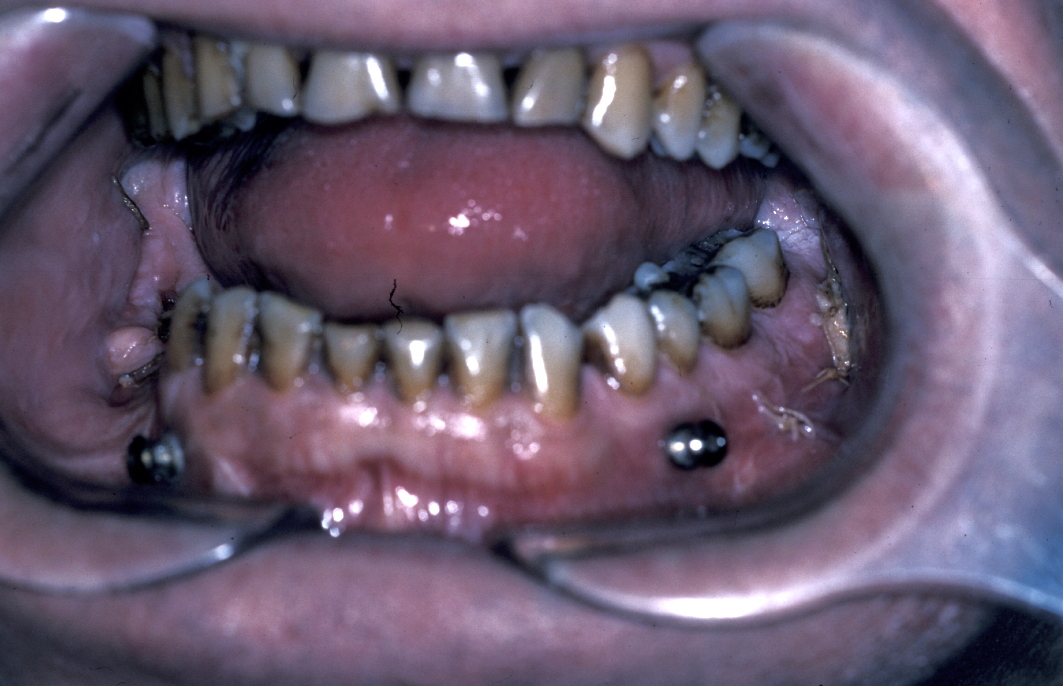

Definitive surgery usually involves open reduction and internal fixation (ORIF) under general anaesthesia, ideally using nasoendotracheal intubation. This allows the patient’s mouth to be closed and the teeth to be manipulated into their normal occlusion. This manipulation helps reduce the mandible into the prefracture bone position. Temporary intermaxillary fixation (IMF) is applied using a variety of techniques (trainee’s hand, eyelets, transalveolar screws (see Figure 1 and Figure 2), ‘rapid IMF’, arch bars). This helps to hold the fracture in its reduced position. Placing a bridle wire or tension band around the teeth can help reduce and temporarily fix the fracture.

Under direct vision via buccal sulcus incisions (incision in the depression between cheek and arch of jaw) the mandibular fracture is exposed and reduction confirmed (see Figure 3).